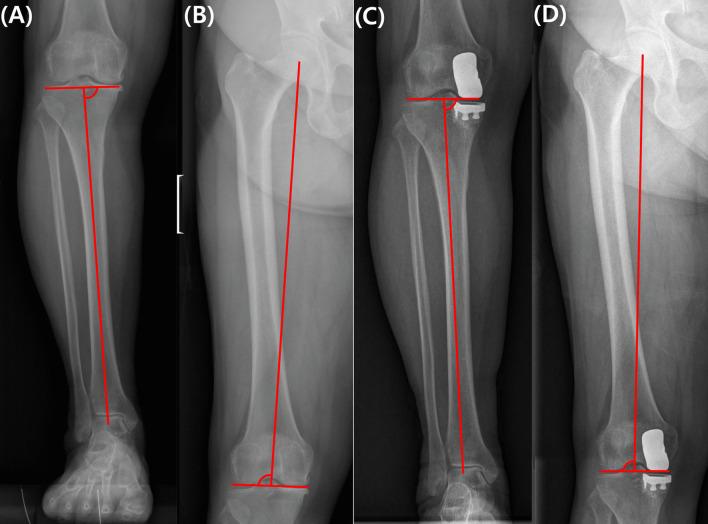

The optimal alignment target for unicompartmental knee arthroplasty (UKA) remains controversial, and literature suggests that its impact on patient-reported outcome measures (PROMs) varies. The purpose of this study was to identify the relationship between changes in the coronal plane alignment of the knee (CPAK) and PROMs in patients who underwent UKA.

A retrospective analysis of 164 patients who underwent UKA was conducted. The types of CPAK types categorized into unchanged, minor (shift to an adjacent CPAK type, e.g., type I to II or type I to IV), and major changes (transitioning to a nearby diagonal CPAK type or two types across, such as type I to V or type I to III). PROMs were assessed preoperatively and 1 year postoperatively using the Hospital for Special Surgery (HSS) scores, Knee Society (KS) scores, Western Ontario and McMaster Universities Osteoarthritis Index (WOMAC), and Forgotten Joint Scores (FJS). Comparison was performed between patients who experienced and who did not experience any changes in the CPAK.

Patients with preserved native CPAK alignment demonstrated significantly superior 1 year postoperative outcomes, with higher HSS, KS knee, and WOMAC pain scores (p = 0.042, p = 0.009, and p = 0.048, respectively). Meanwhile, the degree of change in CPAK did not significantly influence the PROMs, and patients who experienced minor and major changes in the CPAK showed comparable outcomes.

Preserving the native CPAK in UKA procedures is important for achieving favorable clinical outcomes at 1 year postoperative. The extent of change in the CPAK type exerted a limited impact on PROMs, thus emphasizing the importance of change in alignment itself.